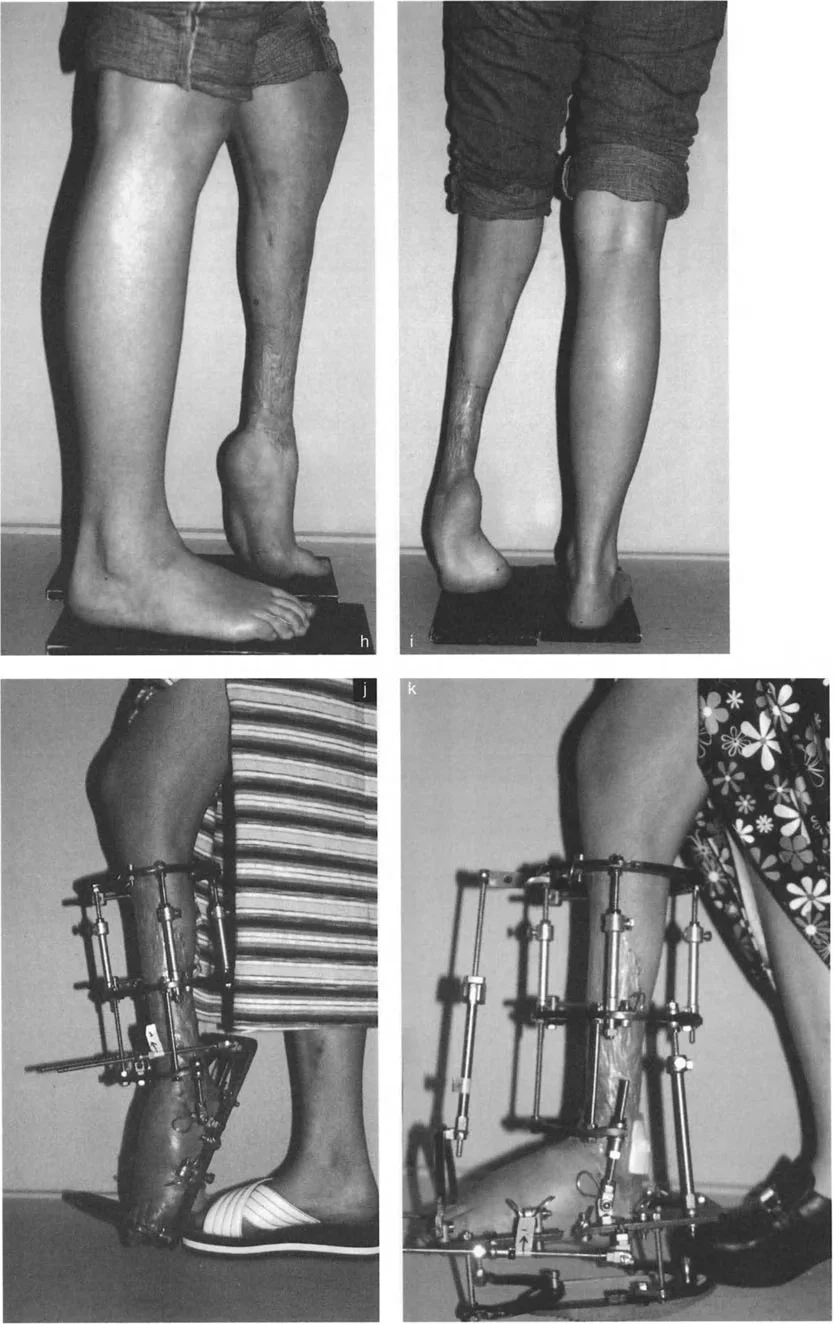

- صعوبة في المشي (العرج): يعتبر هذا من أبرز الأعراض، حيث يجد المريض صعوبة في وضع الكعب على الأرض بشكل طبيعي، مما يجعله يمشي على مقدمة القدم أو جانبها.

- تشوه واضح في شكل القدم أو الكاحل: قد يلاحظ المريض أو المحيطون به تغيرًا في شكل القدم، مثل ارتفاع القوس بشكل مفرط في حالة القدم الجوفاء، أو انحراف الكاحل.

تؤثر هذه الأعراض بشكل مباشر على جودة حياة المريض، وتحد من قدرته على ممارسة الأنشطة اليومية والرياضية. لذلك، فإن التشخيص المبكر والعلاج الفعال ضروريان لتجنب المضاعفات طويلة الأمد واستعادة الوظيفة الطبيعية للقدم والكاحل. يعتمد الأستاذ الدكتور محمد هطيف على تقييم شامل للأعراض والتاريخ المرضي لتحديد أفضل نهج تشخيصي وعلاجي لكل مريض.

خيارات علاج تقوس وتشوهات الكاحل والقدم

يعتمد علاج تشوهات الكاحل والقدم على السبب الكامن وراء التشوه وشدته، بالإضافة إلى عمر المريض وحالته الصحية العامة. يقدم الأستاذ الدكتور محمد هطيف مجموعة واسعة من الخيارات العلاجية، بدءًا من التدخلات التحفظية وصولًا إلى الجراحات المتقدمة باستخدام أحدث التقنيات.

ومع ذلك، في العديد من حالات تقوس الكاحل المعقدة والتشوهات الهيكلية، يكون التدخل الجراحي ضروريًا لتحقيق التصحيح الكامل واستعادة الوظيفة.

التدخلات الجراحية المتقدمة

يتمتع الأستاذ الدكتور محمد هطيف بخبرة واسعة في إجراء مجموعة متنوعة من العمليات الجراحية لتصحيح تشوهات الكاحل والقدم، بما في ذلك: